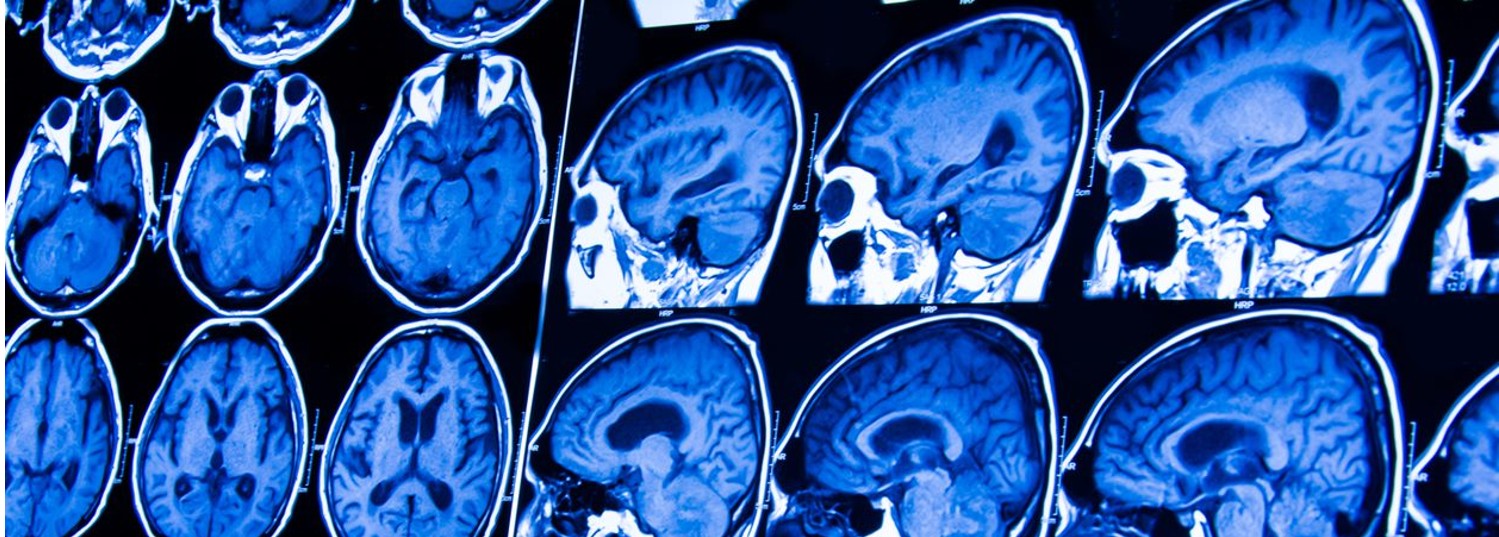

Our lab is committed to understanding diseases of blood vessels in the head and neck using new imaging techniques. We study a variety of diseases, including vasculitis, dissections and connective tissue disorders, but much of our work has targeted atherosclerotic plaque. An important goal of our lab has been to reduce the risk of stroke by understanding how atherosclerotic plaque forms and why it becomes unstable using high-resolution MRI scans of arteries in the head and neck.

We have developed and implemented MRI techniques in population-based studies (e.g., MESA, ARIC) for this purpose. For example, this was done in the MESA cohort and ARIC cohort to understand the risk factors for developing various components of carotid plaque, some of which we know can lead to stroke. A new 3D MRI technique has more recently been developed and implemented in the ARIC cohort to study plaque forming in arteries in the head.

Through continued work with MRI and other new imaging tools, we hope to further understand the basis of plaque development and disruption so we can work to prevent strokes and to gain new insight into the diagnosis and management of vascular diseases affecting blood vessels of the head and neck.